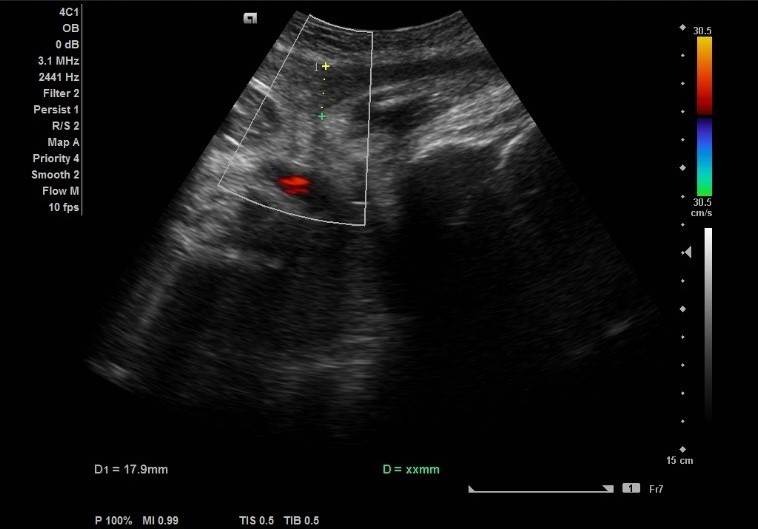

Exames de Ultrassonografia

Exames de Ultrassonografia

Exames de Ultrassonografia

Exames de Ultrassonografia

Exame Ultrassom

Diagnósticos MédicosDescubra o exame ultrassom da SUA IMAGEM MEDICINA DIAGNÓSTICA e certifique-se do comprometimento, eficiência e dedicação dos nossos especialistas. Visando conquistar a excelência, priorizamos a sua...

Exames de Ultrassonografia

Exames de Ultrassonografia